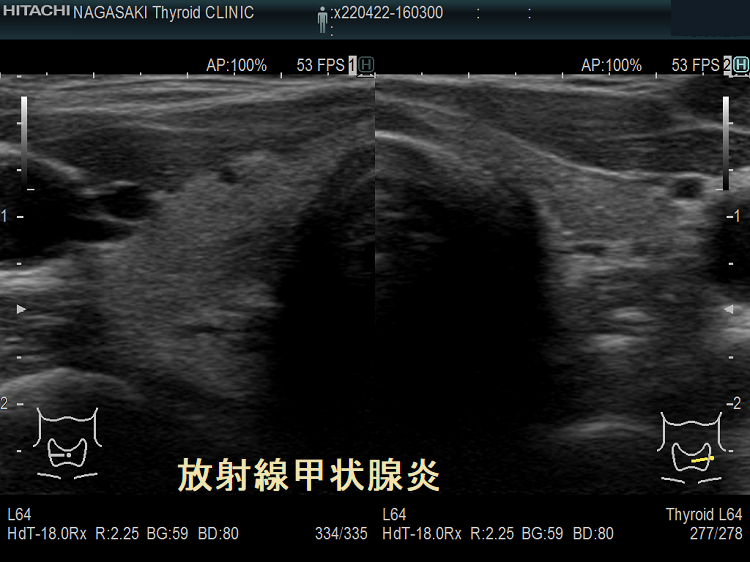

放射線甲状腺炎は、甲状腺以外の癌(頭頚部癌、頭頚部の悪性リンパ腫、頭頚部が照射野に入る肺癌・食道癌・乳癌など)に対する放射線外照射(体の外から放射線を当てる事)が原因で起こります。

放射線量により発症までの期間は異なり、数か月〜数十年後とされます。外部からの放射線量が26 Gyを超えて甲状腺組織の破壊が強いと、甲状腺は萎縮し甲状腺機能低下症に至ります。

子宮頸がん頸部リンパ節転移に放射線外照射した後の放射線甲状腺炎 超音波(エコー)画像 超音波(エコー)画像 (拡大);内部は等エコー、比較的均一。